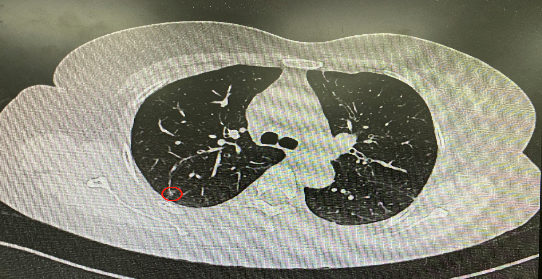

今年54歲的李女士(化名)7月初突然出現(xiàn)右上部腹痛,起初并未在意,以為稍作休息就會好轉(zhuǎn),但疼痛卻并未消退,持續(xù)了一個星期。李女士實在難以忍受,才在家人陪伴下來到西安國際醫(yī)學中心醫(yī)院就診。胸外科二病區(qū)崔凱主任接診患者后,詳細詢問病情并查閱檢查資料,經(jīng)胸部HRCT檢查,結(jié)果提示:右肺上葉后段混合密度結(jié)節(jié)影,考慮原位癌可能,即將患者收入胸腔外科二病區(qū)住院治療。

經(jīng)與患者家屬溝通,崔凱主任決定行外科手術(shù)治療。為達到精準切除,術(shù)前需進行肺小結(jié)節(jié)切除前定位。由于結(jié)節(jié)位于右肺上葉后段,傳統(tǒng)經(jīng)胸外穿刺術(shù)無法抵達病灶。崔凱主任與呼吸內(nèi)科一病區(qū)歐陽海峰主任討論后,決定擬行LungPro全肺診療導航下染色定位。即術(shù)前通過Lung Pro導航規(guī)劃染色位置,經(jīng)Lung Pro實時引導支氣管鏡抵達既定位置,注入亞甲藍染色劑標記結(jié)節(jié)位置。

使用術(shù)前規(guī)劃系統(tǒng)重建全肺3D模型,并于外科醫(yī)生討論染色位置,最終確定標記染色點—右肺上葉后段b亞段(RB2b)。術(shù)中使用P290(4.9mm外徑)標準支氣管鏡,根據(jù)導航術(shù)前規(guī)劃路徑,Lung Pro實時導航下,GS鞘管進入RB2b遠端官腔外病灶并注射亞甲藍染色劑。

一切準備就緒,7月15日,崔凱主任團隊聯(lián)合歐陽海峰主任團隊為患者行單孔胸腔鏡下右肺上葉后段切除術(shù),手術(shù)用時128分鐘順利完成。進入胸腔后,亞甲藍染色部位明顯,患者發(fā)生癌變的右肺上葉后段被成功切除。術(shù)后標本根據(jù)染色部位迅速找到結(jié)節(jié),剖開位置兼染色位置和病灶完全符合,行術(shù)中冰凍后快速送病理檢查。經(jīng)術(shù)后病理檢查,明確診斷為(右肺上葉)原位腺癌。